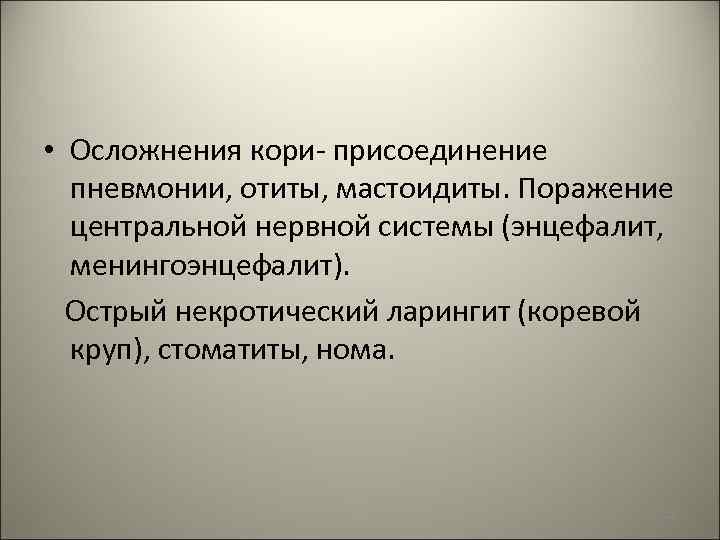

• Осложнения кори- присоединение пневмонии, отиты, мастоидиты. Поражение центральной нервной системы (энцефалит, менингоэнцефалит). Острый некротический ларингит (коревой круп), стоматиты, нома. 108

Коревой энцефалит 109